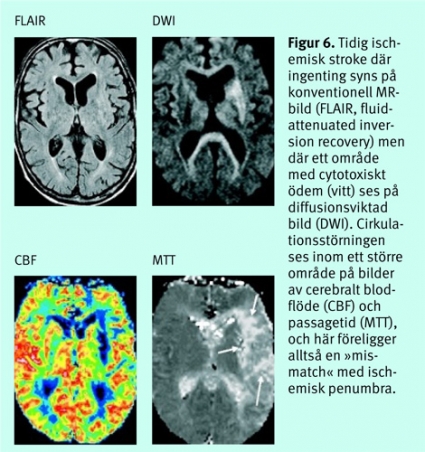

Akut avbildning av cirkulationsfysiologi. Neuronal vävnad nedströms en tromb eller embolus försörjs ofta mycket snabbt av kollaterala blodflöden från angränsande kärlområden, och vid omkring 70–80 procent av alla större infarkter finns områden som överlever med hjälp av dessa reservmekanismer. I sådana regioner kan nervvävnaden ha nedsatt eller upphävd elektrisk aktivitet som följd av att perfusionstrycket inte räcker till. Områden med sådana »förstummade« neuron tenderar ofta att infarcera om inte blodflödet snabbt restitueras. (Neuron med upphävd elektrisk funktion tros kunna överleva i detta tillstånd i 2–3 timmar [8].) Att rädda sådana regioner som ännu inte skadats ohjälpligt (ischemisk penumbra) är en central målsättning för nutida, aktiv behandling vid hjärninfarkt, och tiden att rädda hjärnvävnad är således knapp.

Kliniskt använda neuroradiologiska tekniker för att bedöma perfusionen baseras på att koncentrationen av ett kontrastmedel i hjärnans mikrocirkulation följs med en serie upprepade DT- eller MR-bilder, med 1,5–3 sekunders intervall, under 30–40 sekunder efter en snabb och välkontrollerad intravenös kontrastbolus [9, 10]. Efter bearbetning av bildmaterialet beräknas blodvolym (CBV), blodflöde (CBF) och passagetid (MTT, mean transit time = CBV/CBF) i en arbetsstation, och resultaten presenteras som bildkartor. Beräkningar med DT-teknik kan ge kvantitativa värden, medan MR-tekniken ger relativa värden beroende på svårigheter att exakt följa artärkoncentrationen av kontrastmedlet. Avvikelser som homogent drabbar hela hjärnan är därför svåra att avslöja.

Vid en cirkulationsstörning sker först en ökning av CBV för att kompensera för sänkt perfusionstryck (autoregulation). Vid ytterligare sänkt perfusionstryck sjunker CBF och därefter både CBV och CBF. Vid analysen görs i allmänhet en jämförelse med den friska sidan. Vid DT-perfusion kan penumbraområdet beräknas genom analys av graden av perfusionsstörning (Figur 5).Vid MR-perfusion används samma princip, men man kan där också illustrera penumbraområdet genom subtraktion från området med cirkulationsstörning av området med cytotoxiskt ödem på diffusionsviktade bilder. När man har en »mismatch«, dvs större vävnadsvolym med cirkulationsstörning än området med cytotoxiskt ödem, föreligger en situation där det finns vävnad (penumbra) som potentiellt kan räddas från vävnadsdöd (Figur 6).